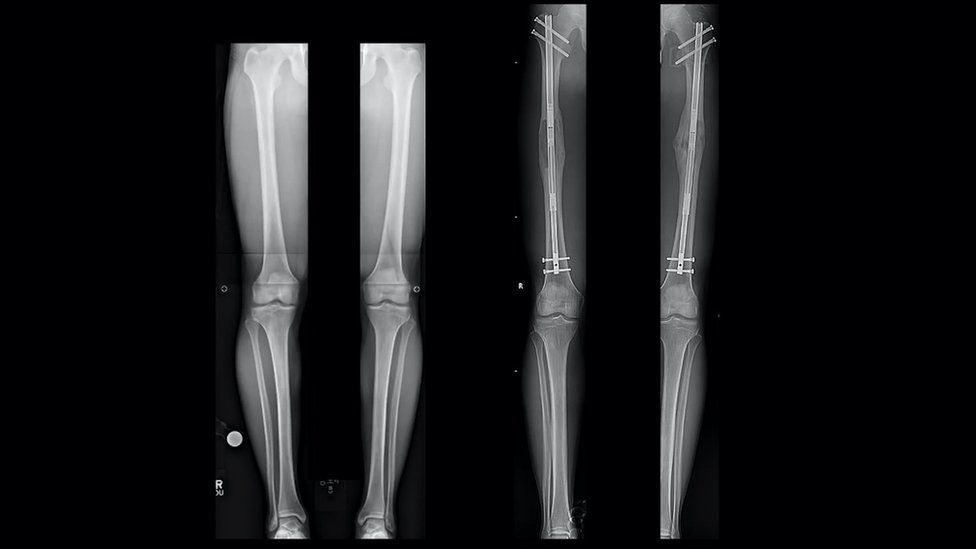

Hình chụp X-quang chân của Sam trước (trái) và sau (phải) ca phẫu thuật. Ảnh: S.Robert Rozbruch.